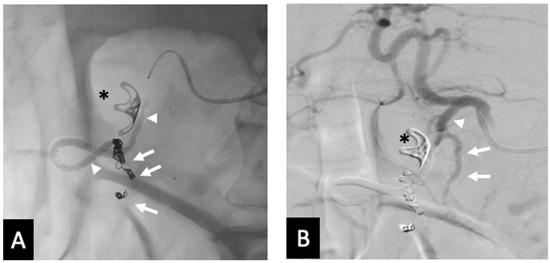

In the two clinical failures, inadequate embolization was performed. Specifically, the GDA was not occluded proximally to its origin in one patient, leaving the SPDA patent, which led to rebleeding which was subsequently embolized with coils (Figure 5). The second patient required a second embolization to address collateral flow from the pancreatico duodenal arcade (Figure 6). This was thought to be due to inadequate distal placement of the backstop coil into the proximal RGEA. It is also worth noting that in one patient small fragments of Ta-OCE entered the hepatic artery due to rapid microcatheter movement with no clinical adverse events observed (Figure 6B). Of note, no ischemic bowel was noted. At 6 months, 9 of 10 patients did not require additional embolization, indicating durable clinical outcomes. One patient died due to complications from an invasive tumor, unrelated to the embolization procedure.

Figure 6. Rebleed example of unembolized RGEA—(A) Pre-embolization radiograph demonstrating the GDA and endoluminal clip placed by during endoscopy (*). (B) A single coil was placed in distal GDA, with Ta-OCE extending to proximal GDA (arrowheads). (C) Repeat angiography from the SMA approach upon the patient’s continued UGI bleeding demonstrated patent collateral flow from the posterior pancreaticoduodenal arcade (arrow). (D) Follow-up CT obtained between the 2 embolization procedures demonstrating separation of Ta-OCE (arrowhead) and embolization of branch hepatic arteries. Image obtained from patient’s chart. Source: NK.